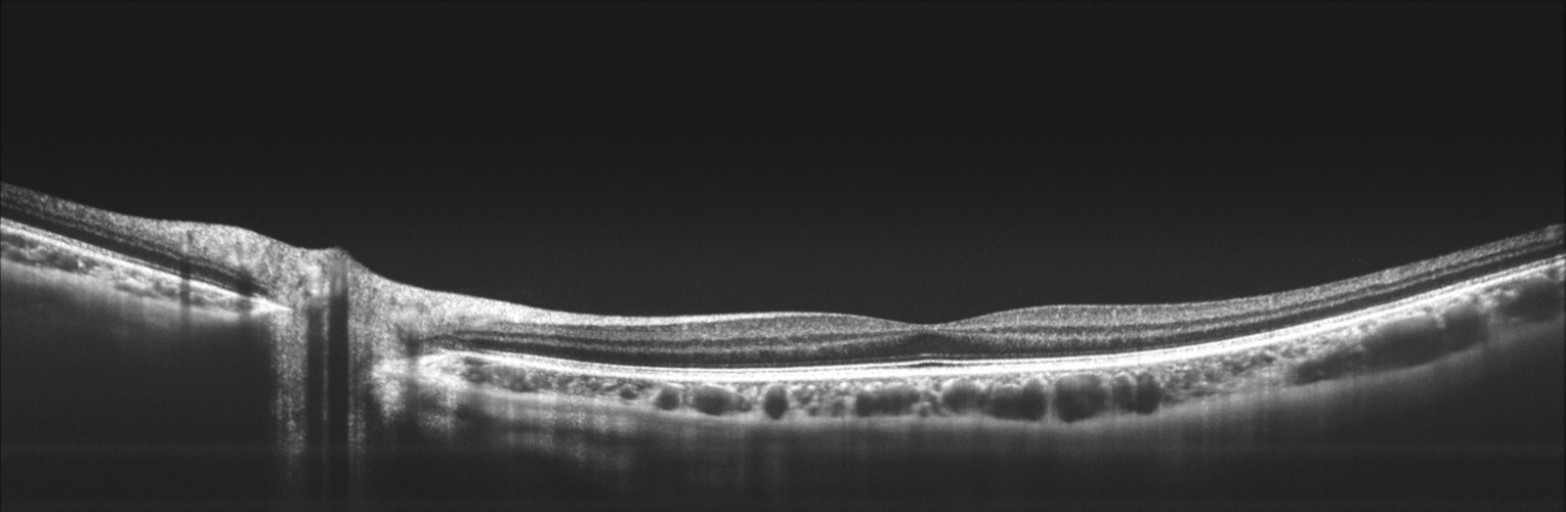

16mm视盘-黄斑区断层成像(团队供图)